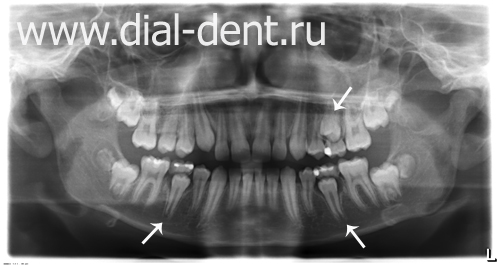

Дентальные снимки и диагностика кариеса